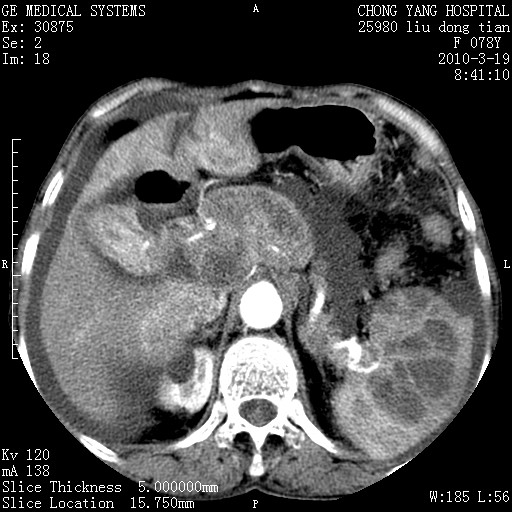

标题: CT25199:F 78Y 腹胀半年 消瘦乏力 [打印本页]

胆囊壁增厚并明显强化,胆囊癌伴多发转移瘤可能性大,淋巴瘤不除外,右肾囊肿,胸腹水.

考虑nhl,肝、脾、腹膜腔及腹膜后多发淋巴结受侵,腹水,右肾囊肿,慢性胆囊炎,右侧少量胸腔积液。

胰头有肿块形成,胰头ca伴肝脾、腹膜腹膜后转移

胆囊有软组织影有强化,支持胆囊癌,肝脾、腹膜后淋巴结转移。

nhl的淋巴结多围绕主动脉,而且主动脉会移位,所以不考虑nhl。

分开来讲:肝左叶、尾叶病灶有不均强化像肝癌;

脾脏病灶无强化,像多发囊肿或淋巴管瘤,不除外淋巴瘤(低强化);

胆囊增生性病变:胆囊癌,腺肌增生症,慢性胆囊炎;

肝门、胰腺头、腹膜后多个团块: 淋巴瘤,转移;

腔静脉肝内段细小有无布加可能?

一元论最好了 淋巴瘤所致改变; 胆囊癌转移不像,胆囊周围肝组织清晰,肝癌淋巴结转移?三元论都不止。

胰头ca伴肝脾、腹膜腹膜后转移!

最后报的胰头癌多发转移,脾脏单独考虑囊肿或淋巴管瘤。